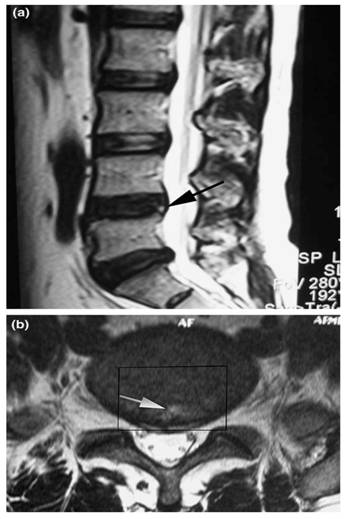

Figure 3

Sagittal T2-weighted magnetic resonance image (MRI) shows a high-intensity zone (arrow) within the posterior annulus at L4-L5 (a). Axial T2-weighted MRI shows a high-intensity zone (arrow) within the posterior annulus at L4-L5 (b). The rectangle indicates the range of disc excision (PLIF procedure) that is used for histological examination (Adopted from Baogan Peng et al. [26]).